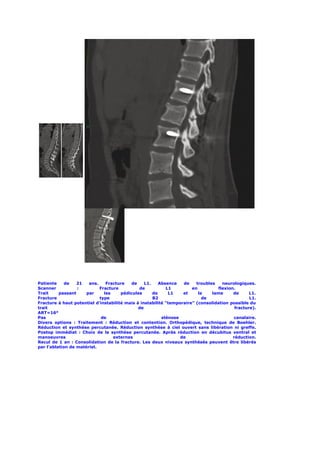

Patiente de 19 ans, fracture de L2. Absence de trouble neurologique.

Scanner : Absence de signes de rotation ou de distraction.

Fracture                              type                                 A3.1

ART                                   =                                     22°

Sténose                            canalaire                               50%

Divers                     options                       :

Traitement           :          Réduction             et            contention.

Orthopédique,               technique                 de                boehler

Synthèse percutanée puis scanner postopératoire afin d’évaluer la

nécessité               de                  greffe                   antérieure

Réduction et synthèse à ciel ouvert associées à une greffe postérolatérale

pontant          le         disque            lésé            (T12          L1)

Synthèse     et  greffe   structurelle    par    voie    antérieurs     unique.

Postop                    immédiat                         :

Choix du traitement percutané associé à une greffe antérieure. Synthèse

L2,                             L4                                  percutanée.

La réduction est obtenue par l’installation et les manœuvres de réduction

externe                                                          peropératoire.

Une greffe antérieure est d’emblée associée du fait de la comminution de

la   fracture   et  donc    du    risque   de     perte      de   correction.

Une greffe intersomatique L2 L3 structurelle est réalisée. Réalisée par

lombotomie gauche qui est préférée à la voie antérieure pure pour les

étages au dessus du disque L2 L3.

Scanner                     post                    opératoire                    :

Restitution          de           la           courbure            physiologique.

Une fois la fusion L2 L3 obtenue, la synthèse pourra être retirée pour libérer l’étage L3 L4

indemne de lésion.